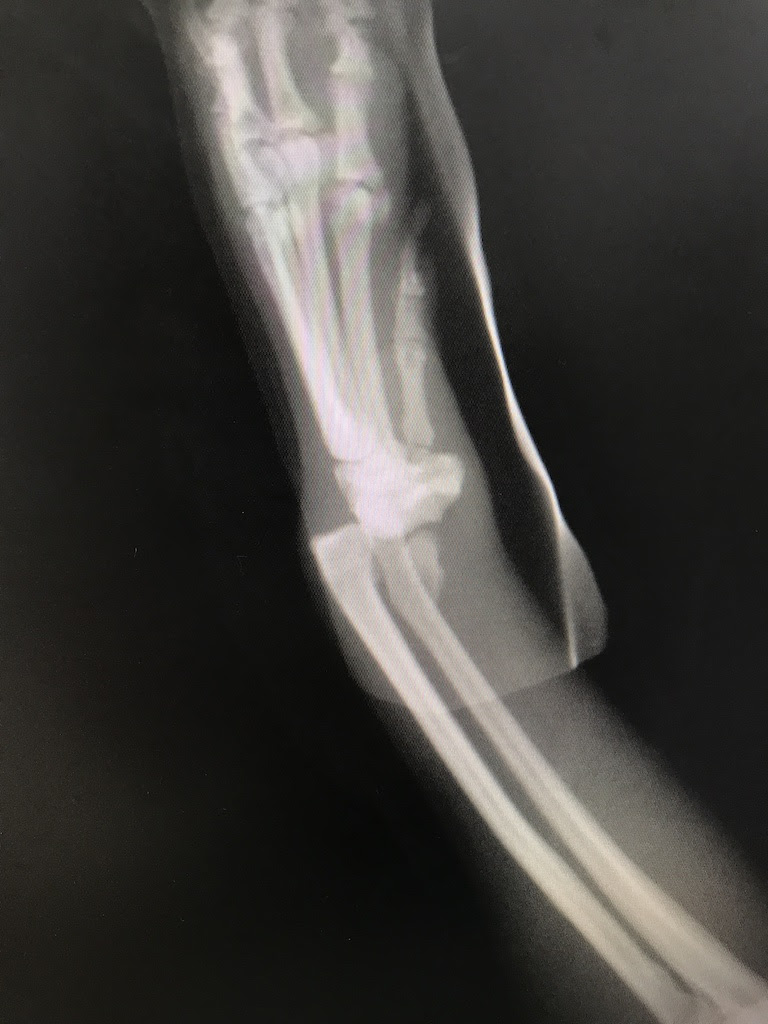

はりねずみ通信 骨折手術 姫路の動物病院かない動物病院